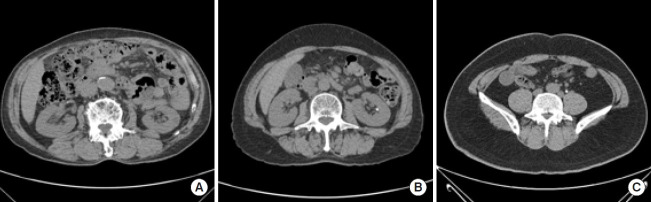

Purpose: Urinary stones cause lateral abdominal pain and are a prevalent condition among younger age groups. The diagnosis typically involves assessing symptoms, conducting physical examinations, performing urine tests, and utilizing radiological imaging. Artificial intelligence models have demonstrated remarkable capabilities in detecting stones. However, due to insufficient datasets, the performance of these models has not reached a level suitable for practical application. Consequently, this study introduces a vision transformer (ViT)-based pipeline for detecting urinary stones, using computed tomography images with augmentation.

Methods: The super-resolution convolutional neural network (SRCNN) model was employed to enhance the resolution of a given dataset, followed by data augmentation using CycleGAN. Subsequently, the ViT model facilitated the detection and classification of urinary tract stones. The model's performance was evaluated using accuracy, precision, and recall as metrics.